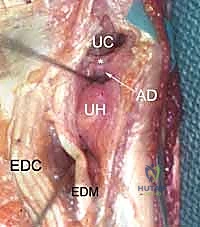

4. The 6U Portal (Ulnar to ECU)

- Location: On the ulnar side of the extensor carpi ulnaris (ECU) tendon.

- Anatomy: Again, the ECU tendon is the key landmark.

- Neurovascular Risks: The dorsal cutaneous branch of the ulnar nerve is at increased risk here. Be mindful of its course.

- Function: Typically used as an outflow portal for irrigation fluid, but can also be used for visualization or instrumentation in specific cases.

Dorsal Distal Radioulnar Joint (DRUJ) Portals

These portals offer direct access to the DRUJ for assessing its articular cartilage and ligaments.

1. The Dorsal Radioulnar Joint Portal (Proximal and Distal)

- Location: Lies between the ECU and the EDM tendons. There can be a proximal (PDRUJ) and a distal (DDRUJ) portal.

- Anatomy: The interval between the fifth (EDM) and sixth (ECU) extensor compartments.

- Neurovascular Risks: Transverse branches of the dorsal cutaneous branch of the ulnar nerve are the only sensory nerves in proximity, typically at a mean of 17.5 mm distally (range 10–20 mm) from the portal. Careful dissection is still advised.

- Function: Used in concert with the volar distal radioulnar portal to fully assess the articular cartilage of the ulnar head and sigmoid notch, and for instrumentation within the DRUJ.